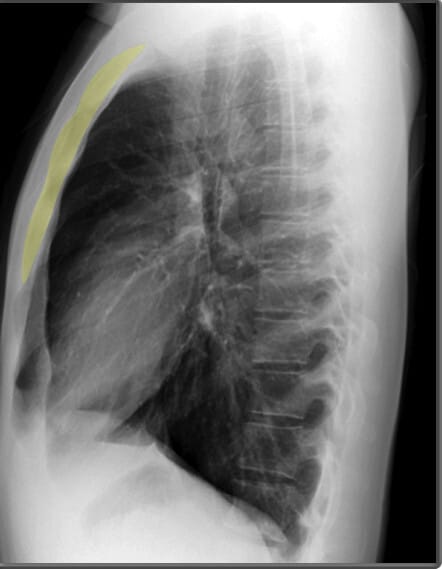

Lateral View of Chest X-ray

측면 영상은 폐, 심장 및 척추의 깊이를 평가하는 데 유용합니다.

| 흉골 (Sternum) |

| ✅ 측면 영상에서 길게 보이며, 정상적으로는 매끄럽고 연속적인 윤곽을 보여야 합니다. 골절이 있는 경우 불연속적인 선이 관찰될 수 있습니다. |

| 척추체 (Vertebral Bodies) |

| ✅ 척추체는 정상적으로 크기와 모양이 균일해야 하며, 압박 골절이나 골 용해 소견이 있으면 병적 상태를 고려해야 합니다. |

| 추궁근 (Pedicles) |

| ✅ 추궁근은 척추의 일부로, 좌우 대칭적으로 나타나야 합니다. 종양이나 감염으로 인해 변형되거나 소실될 경우 병리적 상태를 의심할 수 있습니다. |

하늘색이 Vertebral bodies, 파란색 (코발트 블루)가 Pedicles| 기관 (Trachea) |

| ✅ 흉부 중앙에서 공기가 가득 찬 검은 색의 관 형태로 보이며, 정상적으로는 앞쪽으로 약간 기울어져 있습니다. 협착되거나 편위된 경우 기도 병변을 의심할 수 있습니다. |

| 늑골횡격막각 (Costophrenic Angle) |

| ✅ 늑골과 횡격막이 만나는 각도로, 정상적으로 뚜렷하고 예리하게 보여야 합니다. 둔해지거나 소실되면 흉수(pleural effusion) 가능성을 시사합니다. |